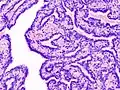

Histopathology of intraductal papilloma of the breast by excisional biopsy. Hematoxylin and eosin stain. -